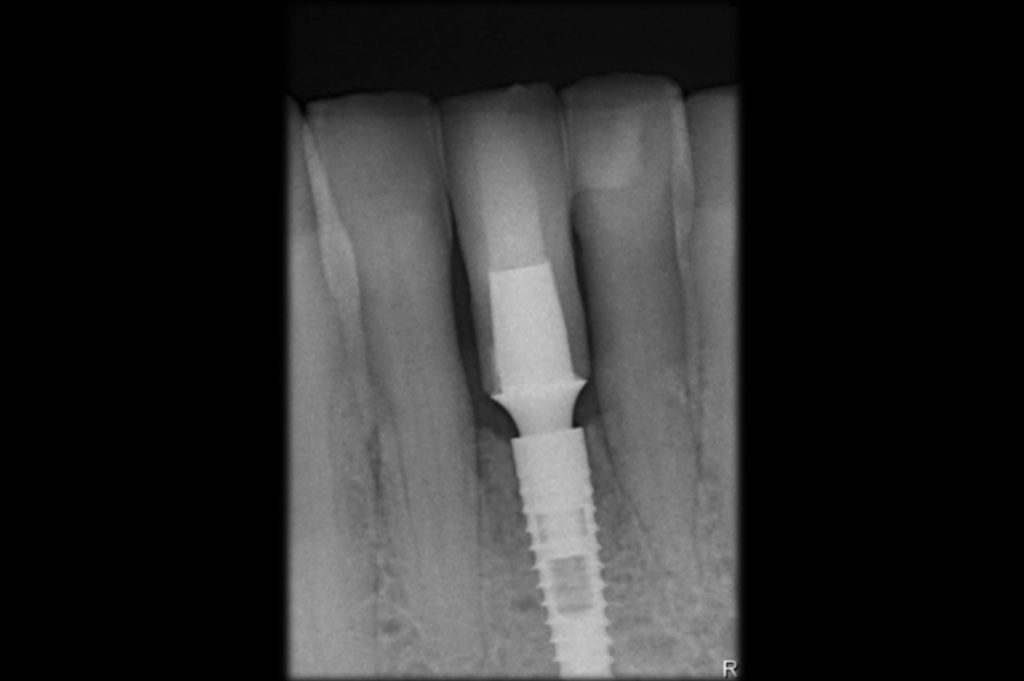

Rx para confirmar el correcto posicionamiento del implante